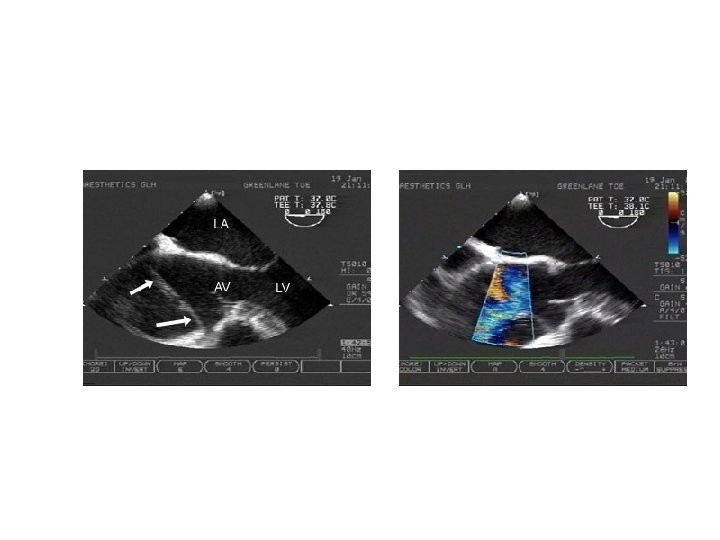

Diagnostica per Immagini(4) Transesophgeal echocaediogram 1. Freely movable flap within the lumen of the vessel 2. Differential Doppler detection of true v. s. false lumen F T Freely movable flap within the aorta